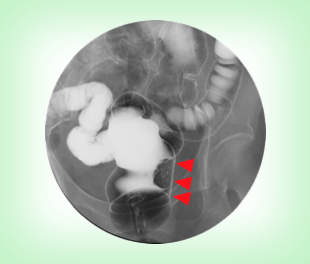

大腸がんは下のような大腸造影検査(注腸検査)、大腸カメラ(大腸内視鏡検査)にて発見、確認することができます。病変の場所、進行の程度により、腸を切る場所や範囲が変わってきます。

左の直腸がんのバリウム検査の写真です。の部位にバリウムをはじく影が見えます。この場所にがんがあるのです。